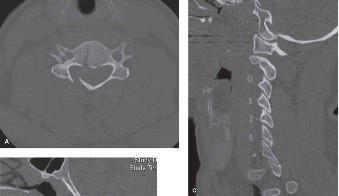

Prognosis of central cord syndrome? Indications for surgery for this disorder? CASE 2 A 56-year-old man presents to you with a chief complaint of severe right buttock, posterior thigh, and lower leg pain for 12 weeks. It radiates to the lateral aspect of his foot, and it is worse with sitting or standing for prolonged periods and with walking. Now over the past 2 weeks, he reports difficulty with toe push-off on the right side. Treatment so far has been nonsteroidal anti-inflammatory drugs (NSAID), physical therapy, and an epidural injection without significant relief. Physical examination findings include 4/5 right ankle plantar flexion, a positive straight leg raise on the right, and an absent right Achilles tendon reflex. Images of his lumbar spine are shown in Figures 1–4 and 1–5.

Figure 1–4

Figure 1–5

The correct answer is (C). The patient presents with classic right S1 radiculopathy and new onset plantar flexion weakness. The images demonstrate a right-sided paracentral disc herniation at L5/S1 compressing the traversing S1 nerve root. Despite nonoperative management, he continues to have severe pain and new weakness. Continued physical therapy or an epidural injection is unlikely to improve the patient’s pain at this time. In the setting of neurological decline, surgery is more strongly indicated. Lumbar discectomy is the most appropriate procedure for this patient. Fusion would only be indicated if there were radiographic signs of instability, which are not present.

Figure 1–8 Mid-sagittal image of the pelvis.

Figure 1–9 Axial image of the pelvis.

Discussion

The correct answer is (D). Critical steps in decision-making include determination of neurologic status, presence of associated pelvic ring injuries, and stability of the lumbopelvic junction. The neurologic examination demonstrates a deficit that is at least in part localized to the sacral nerve roots. In the presence of sacral canal compromise, decompression via laminectomy is indicated. The CT scan demonstrates a U-type injury with a high transverse sacral fracture and bilateral vertical extension through the sacral foramen. In the descriptive classification of sacral fractures in Denis zone 3, H-type and U-type sacral fractures represent spinopelvic dissociation and must be distinguished from fractures localized to the posterior pelvic ring, which are vertically unstable. The spinopelvic junction serves as a critical transitional zone as the axial load of the upper body is distributed from the upper sacrum to the ilium and finally the acetabulum. Surgery is indicated to prevent progressive deformity and chronic pain. Reconstruction should include stabilization from the lumbar spine to the pelvis using a pedicle screw/iliac screw construct. Nonoperative treatment with progressive mobilization is not appropriate for this type of fracture. Plating of the sacrum is not sufficient to restore stability of this injury; nor are sacroiliac screws.